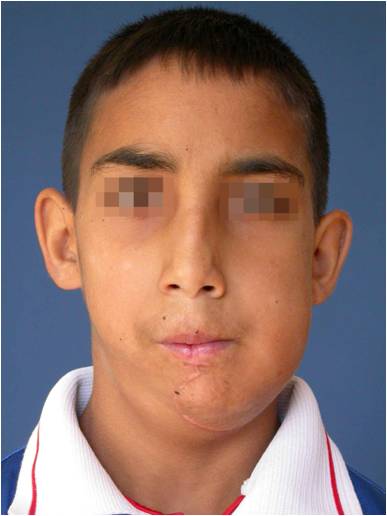

Дете с тумор на долната челюст. Лечението налага нейната резекция. Възстановена е едномоментно чрез микросъдова реконструкция с част от тазова кост. Първата успешна микросъдова долночелюстна реконструкция в България – случай на доц. Джоров.